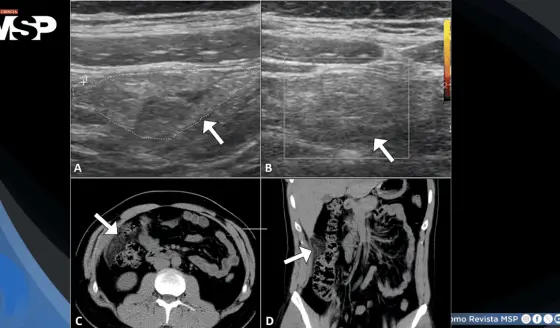

Dolor abdominal severo en paciente de 32 años resultó ser un infarto omental y no apendicitis